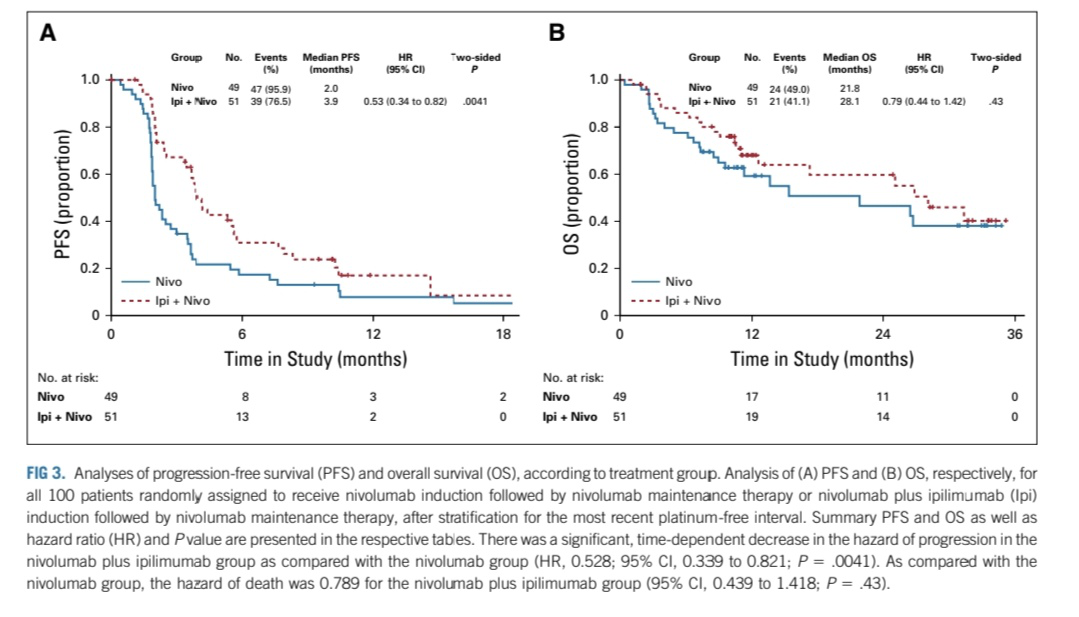

本例患者在铂耐药复发时由于存在化疗相关性血小板减少(CIT),需长期使用TPO受体激动剂,无法加入临床试验,且由于血小板减少症,后线也需选择对血小板影响较小的药物。基于NCCN指南中铂耐药卵巢癌单药化疗方案的推荐,结合患者既往用药方案,选择骨髓抑制较小的白蛋白紫杉醇周疗。患者PD-L1表达(22C3):CPS,2,考虑免疫治疗可能有效。搜索相关文献,在铂耐药卵巢癌中PD-1/PD-L1药物相关临床研究多未见明显获益。但有小样本临床研究发现纳武利尤单抗+伊匹木单抗与单药纳武利尤单抗比较能够延长PFS 1.9个月,延长OS 6.3个月。因此制定个性化治疗方案。白蛋白紫杉醇300mgD1、8、15静脉+顺铂50mgD1、8腹腔化疗+卡度尼利单抗375mgD1、15。剂量密集型抗肿瘤治疗过程中,对患者进行全程管理,对治疗期间各项AE及时有效管理,最终使患者得到长期生存获益。

5. Zamarin, R.A. Burger, M.W. Sill, et al., Randomized phase II trial of nivolumab ver_x0002_sus nivolumab and ipilimumab for recurrent or ersistent ovarian cancer: an NRG oncology study, J. Clin. Oncol. (2020) JCO1902059.